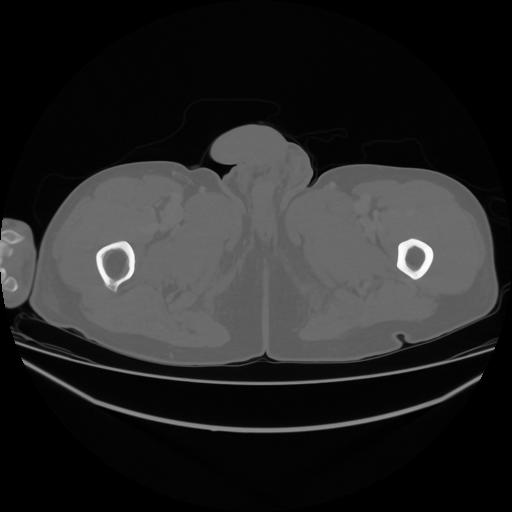

5 CUERPO,CE,Vol,1.0,CUERPO,,